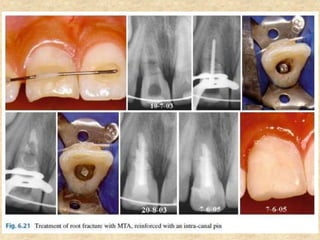

8. Repair of fracture:

• The success rate of horizontal root fracture treatment depending on their

location (cervical, middle, and apical). The root fracture located in the

cervical and middle thirds causes difficulty for treatment because it is

difficult for dental immobilization, leading to injury or even preventing the

consolidation of the fragments.

• For these cases, it is possible to strengthen the tooth with an intra-canal

pin cemented with MTA

• The canal is instrumented, and then an apical plug with MTA is performed.

A metal pin is selected in order to remain adjusted in the canal, which is

filled with MTA, seating the pin inside. Thus, there is reinforcement for the

root, preventing mobility of the coronary segment.